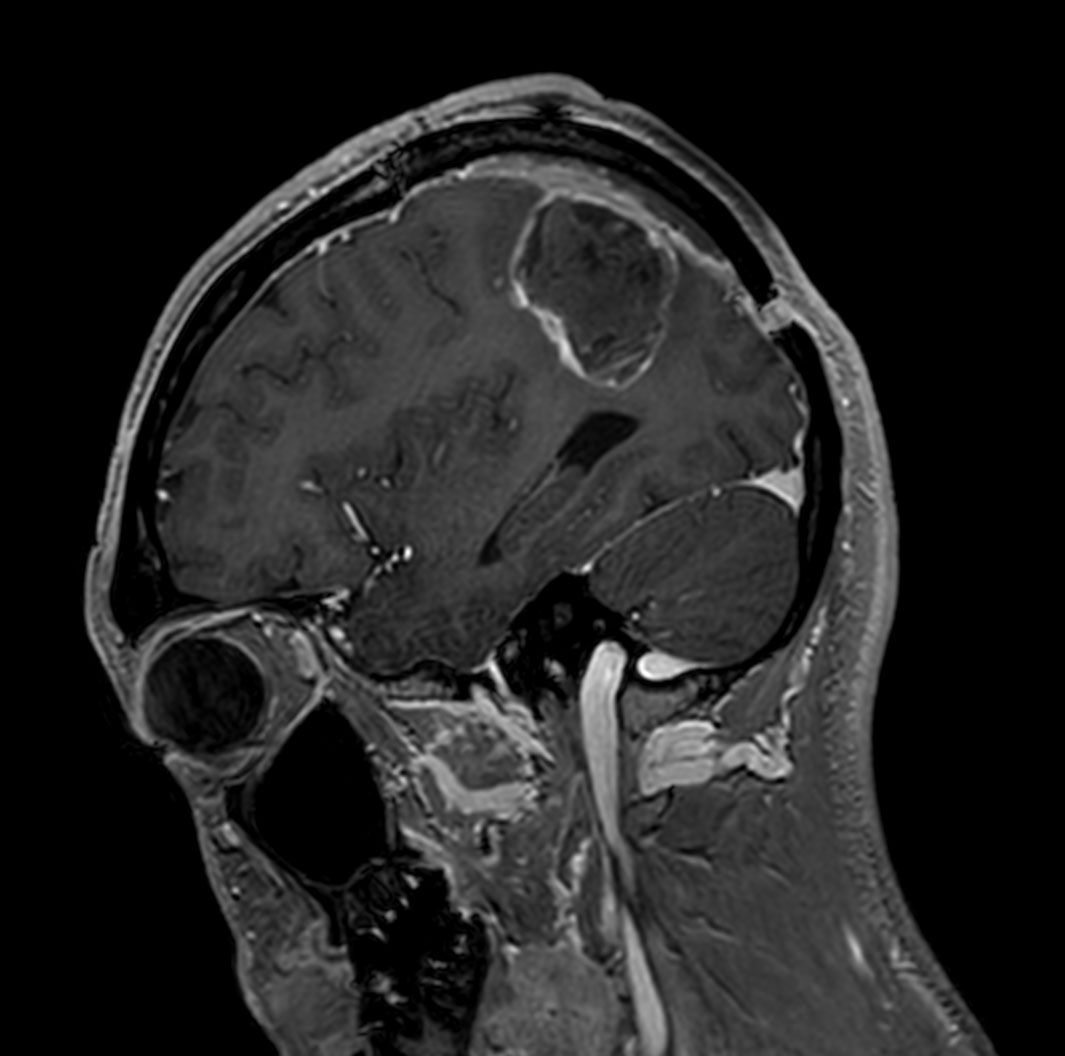

Patient with a glioblastoma recurrence. Glioblastoma was surgically removed 5 month ago. The gadolinium enhancement was first thought to be the enhancement of choroid plexus. However this was diagnosed recurrence of glioblastoma due to the high APT value.

Sagittal T1w 3D FFE with gado